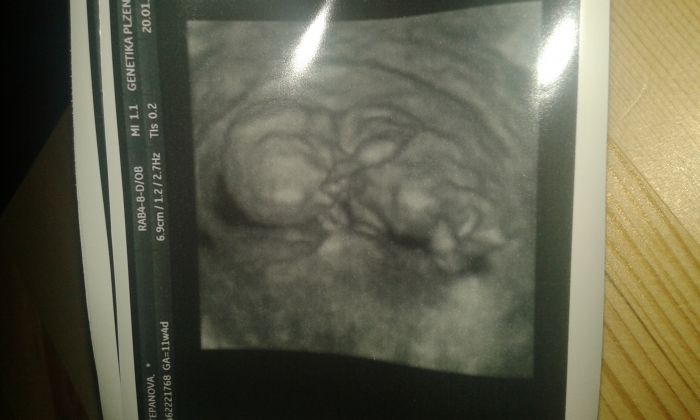

Ahoj holky. .jdu za cama zkusenyma z otázkou. .kdy se dají poznat jednovaječná dvojčata? Byli jsme na prvním screeningu a prostě se nám zda ze je za miminkem jeste jedno a nebo tak mate ten 3D ..ten ultrazvuk byl takový fofr ale mame všechny testy v pořádku. .Prikladam fotecku..a dekuju za názory. ..

Pájo, myslím že se ti to zdá právě proto, že je to 3D ultrazvuk

. A co říkal lékař? Krásné těhotenství přeji!!